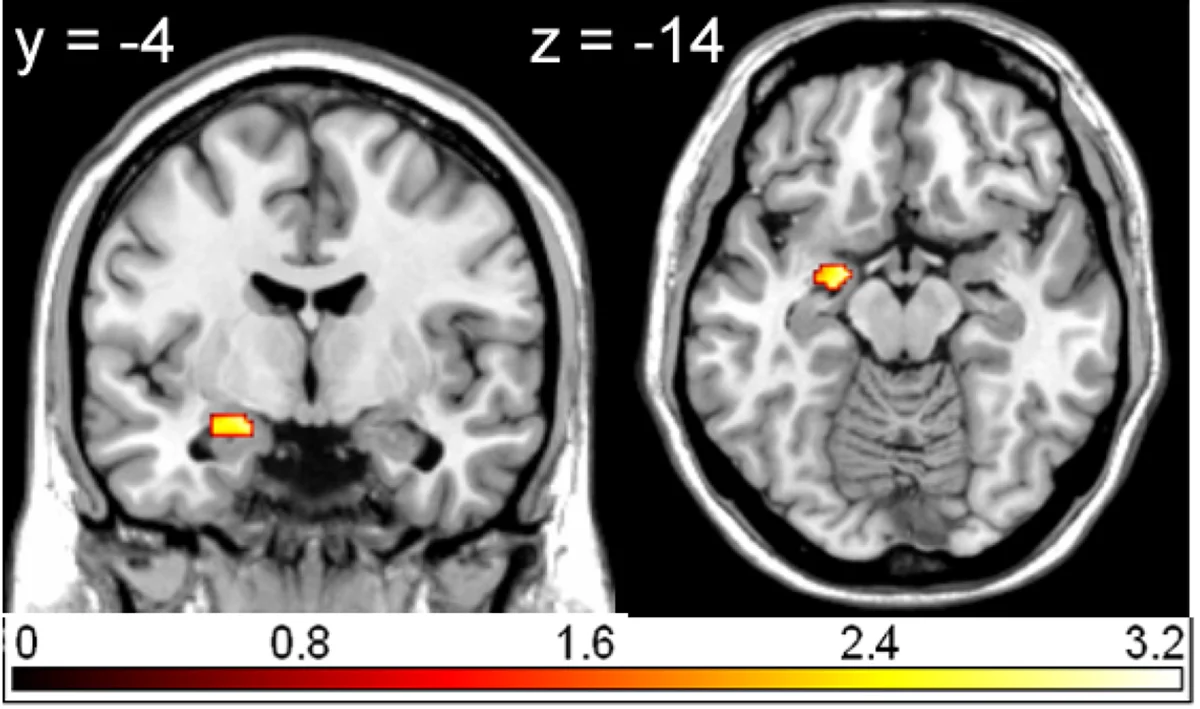

Nově například víme, že dlouhodobý stres přepsává strukturu mozku, ovlivňuje paměť nebo náchylnost k úzkostem. Díky špičkovým MRI přístrojům a spolupráci psychologů s neurovědci máme dnes zcela konkrétní data – nejde už jen o teorie.

Nedávné české experimenty například dokázaly, že amyglada je u lidí s úzkostmi hyperaktivní, zatímco meditace může tento efekt zmírnit. Věděli jste, že čeští adolescenti, kteří pravidelně sportují, mají ve srovnání se spolužáky podstatně klidnější emoční reakce?